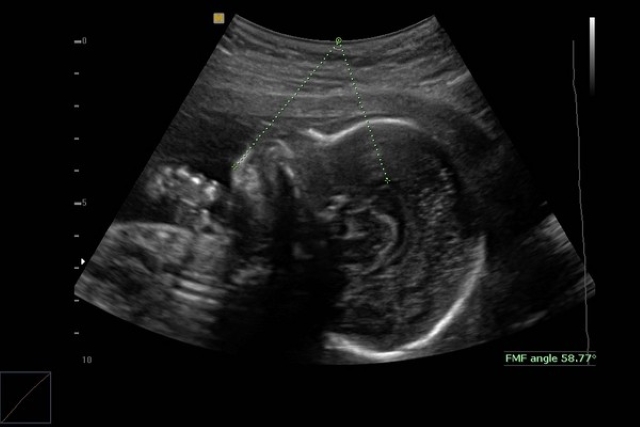

Sau đó, thai phụ được giới thiệu chuyển đến bệnh viện Cheng Hsin General Hospital, tại đây bác sĩ Lý Vỹ Hạo, khoa phụ sản tiếp nhận ca bệnh cũng khuyên cô Đào nên chụp X - quang và xác nhận có một khối u lớn giữa ngực đang chèn ép tim của của thai phụ, được chẩn đoán mắc bệnh ung thư hạch bạch huyết (Lymphoma).